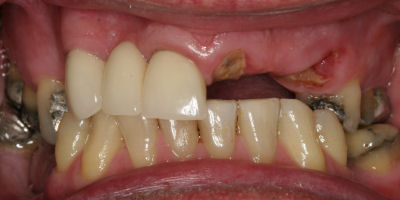

This is an advanced set of dental procedures best carried out by prosthodontists or restorative dentists. Full mouth rehabilitation is a term used in dentistry for rebuilding teeth and supporting structures after decay and gum disease has been stabilised. Full mouth rehabilitation is only required if your bite has collapsed or you have multiple missing or heavily filled teeth. Implants, crown and bridgework and/or partial or full dentures can be used to restore your bite close to its original height. Temporary restorations or dentures are used to get an idea of what the final result will be like before having the final restorations made. Temporary restorations also allow you to have input into your appearance and smile giving you the opportunity to show friends and family what your teeth may look like when the work is complete.

Before/After